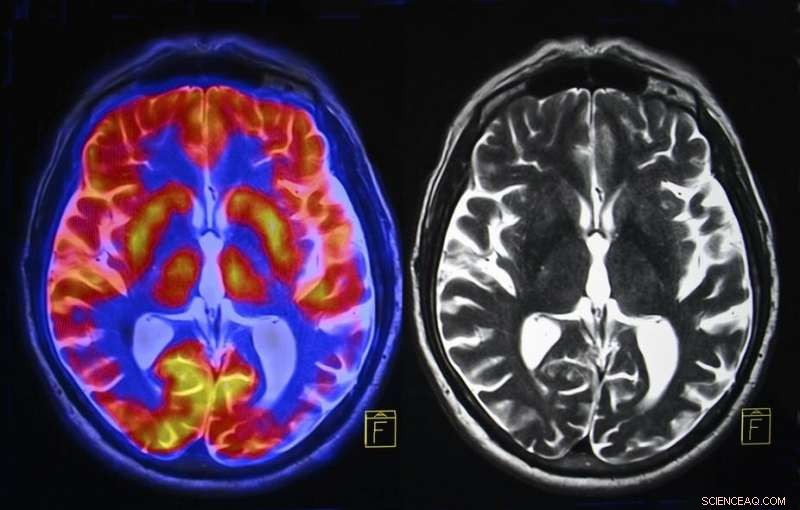

Recent extensive brain imaging of the visual cortex as people read text has provided important insights into how the brain perceives simple patterns. In my new paper, published in the Journal of Archaeological Science Reports, I analyse such research to argue that the earliest human-made patterns were aesthetic rather than symbolic, and describe what that means for the evolution of reading and writing.

In 2000 I first suggested that the way the "early visual cortex" – the location where visual information from the eye first impacts the cortex – processes information gave rise to the ability to engrave simple patterns. We know that this area has neurons coding for edges, lines and "T" junctions. As distilled forms, these shapes preferentially activate the visual cortex.

These developments therefore enabled the brain to reuse the visual cortex for an entirely new purpose. Ultimately, it could have created a new process in the brain that exploited the visual cortex, giving rise to a visual word form area and connecting with speech areas incrementally over time.